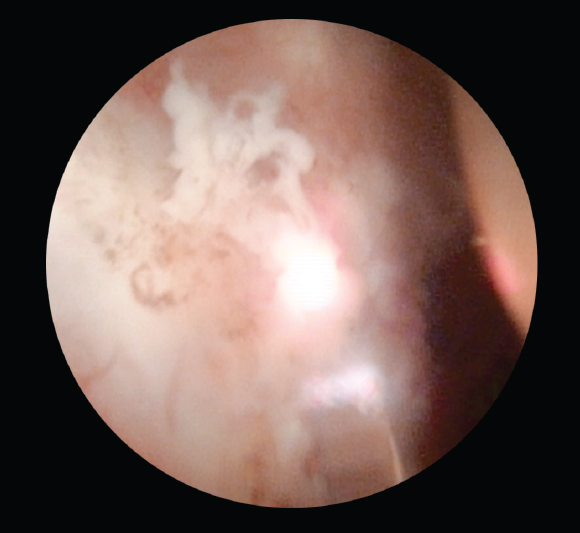

В группу 1 было включено 49 пациентов (средний возраст 62,4 ± 9,0 года), всем больным выполняли классическую ТУРМП с последующим внутрипузырным введением химиопрепарата. Группу 2 составили 48 пациентов (средний возраст 57,7 ± 11,2 года), подвергшихся ТУРМП с последующей Nd:YAG-лазерной абляцией ложа опухоли и введением химиопрепарата в послеоперационном периоде. Оперативные вмешательства проводили под спинальной анестезией. Хирургический этап лечения включал диагностическую уретроцистоскопию, позволяющую оценить состояние мочеиспускательного канала, шейки и слизистой оболочки мочевого пузыря, расположение устьев мочеточников, количество и объем образований. Следующим этапом было выполнение резекции стенки мочевого пузыря с опухолью до мышечной оболочки: использовалась как резекция единым блоком, так и стандартная ТУРМП с использованием различных источников энергии (рис. 1). Заключительный этап — гемостаз различными источниками энергии (биполярная, лазерная), а также абляция ложа опухоли Nd:YAG-лазером у пациентов группы 2 (рис. 2).

Рис. 2. Этап Nd:YAG-лазерной абляции ложа опухоли мочевого пузыря

Fig. 2. Nd:YAG laser ablation of the bladder tumor bed